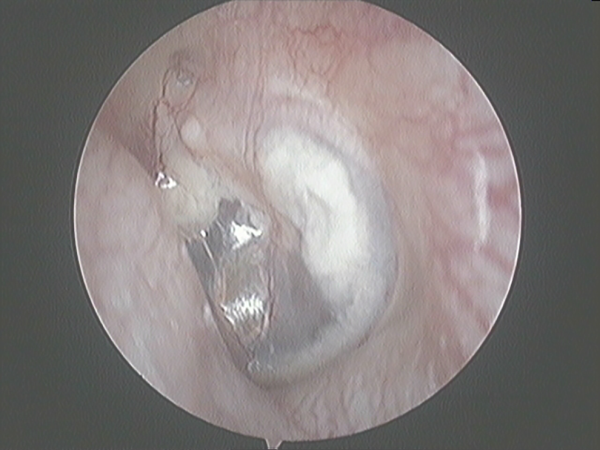

During the first 3 postoperative days, daily outpatient clinic revision was performed to prevent hematoma and to reinsert any displaced grafts. After 3 days, weekly revision was performed during the first month to check and control potential infections. The first hearing test was performed 2 months after and the final test 12 months after the operation (Figure 2). After 12 months, impedanciometry was performed to ensure TM compliance.

Figure 2

Tympanic membrane after one year PO.